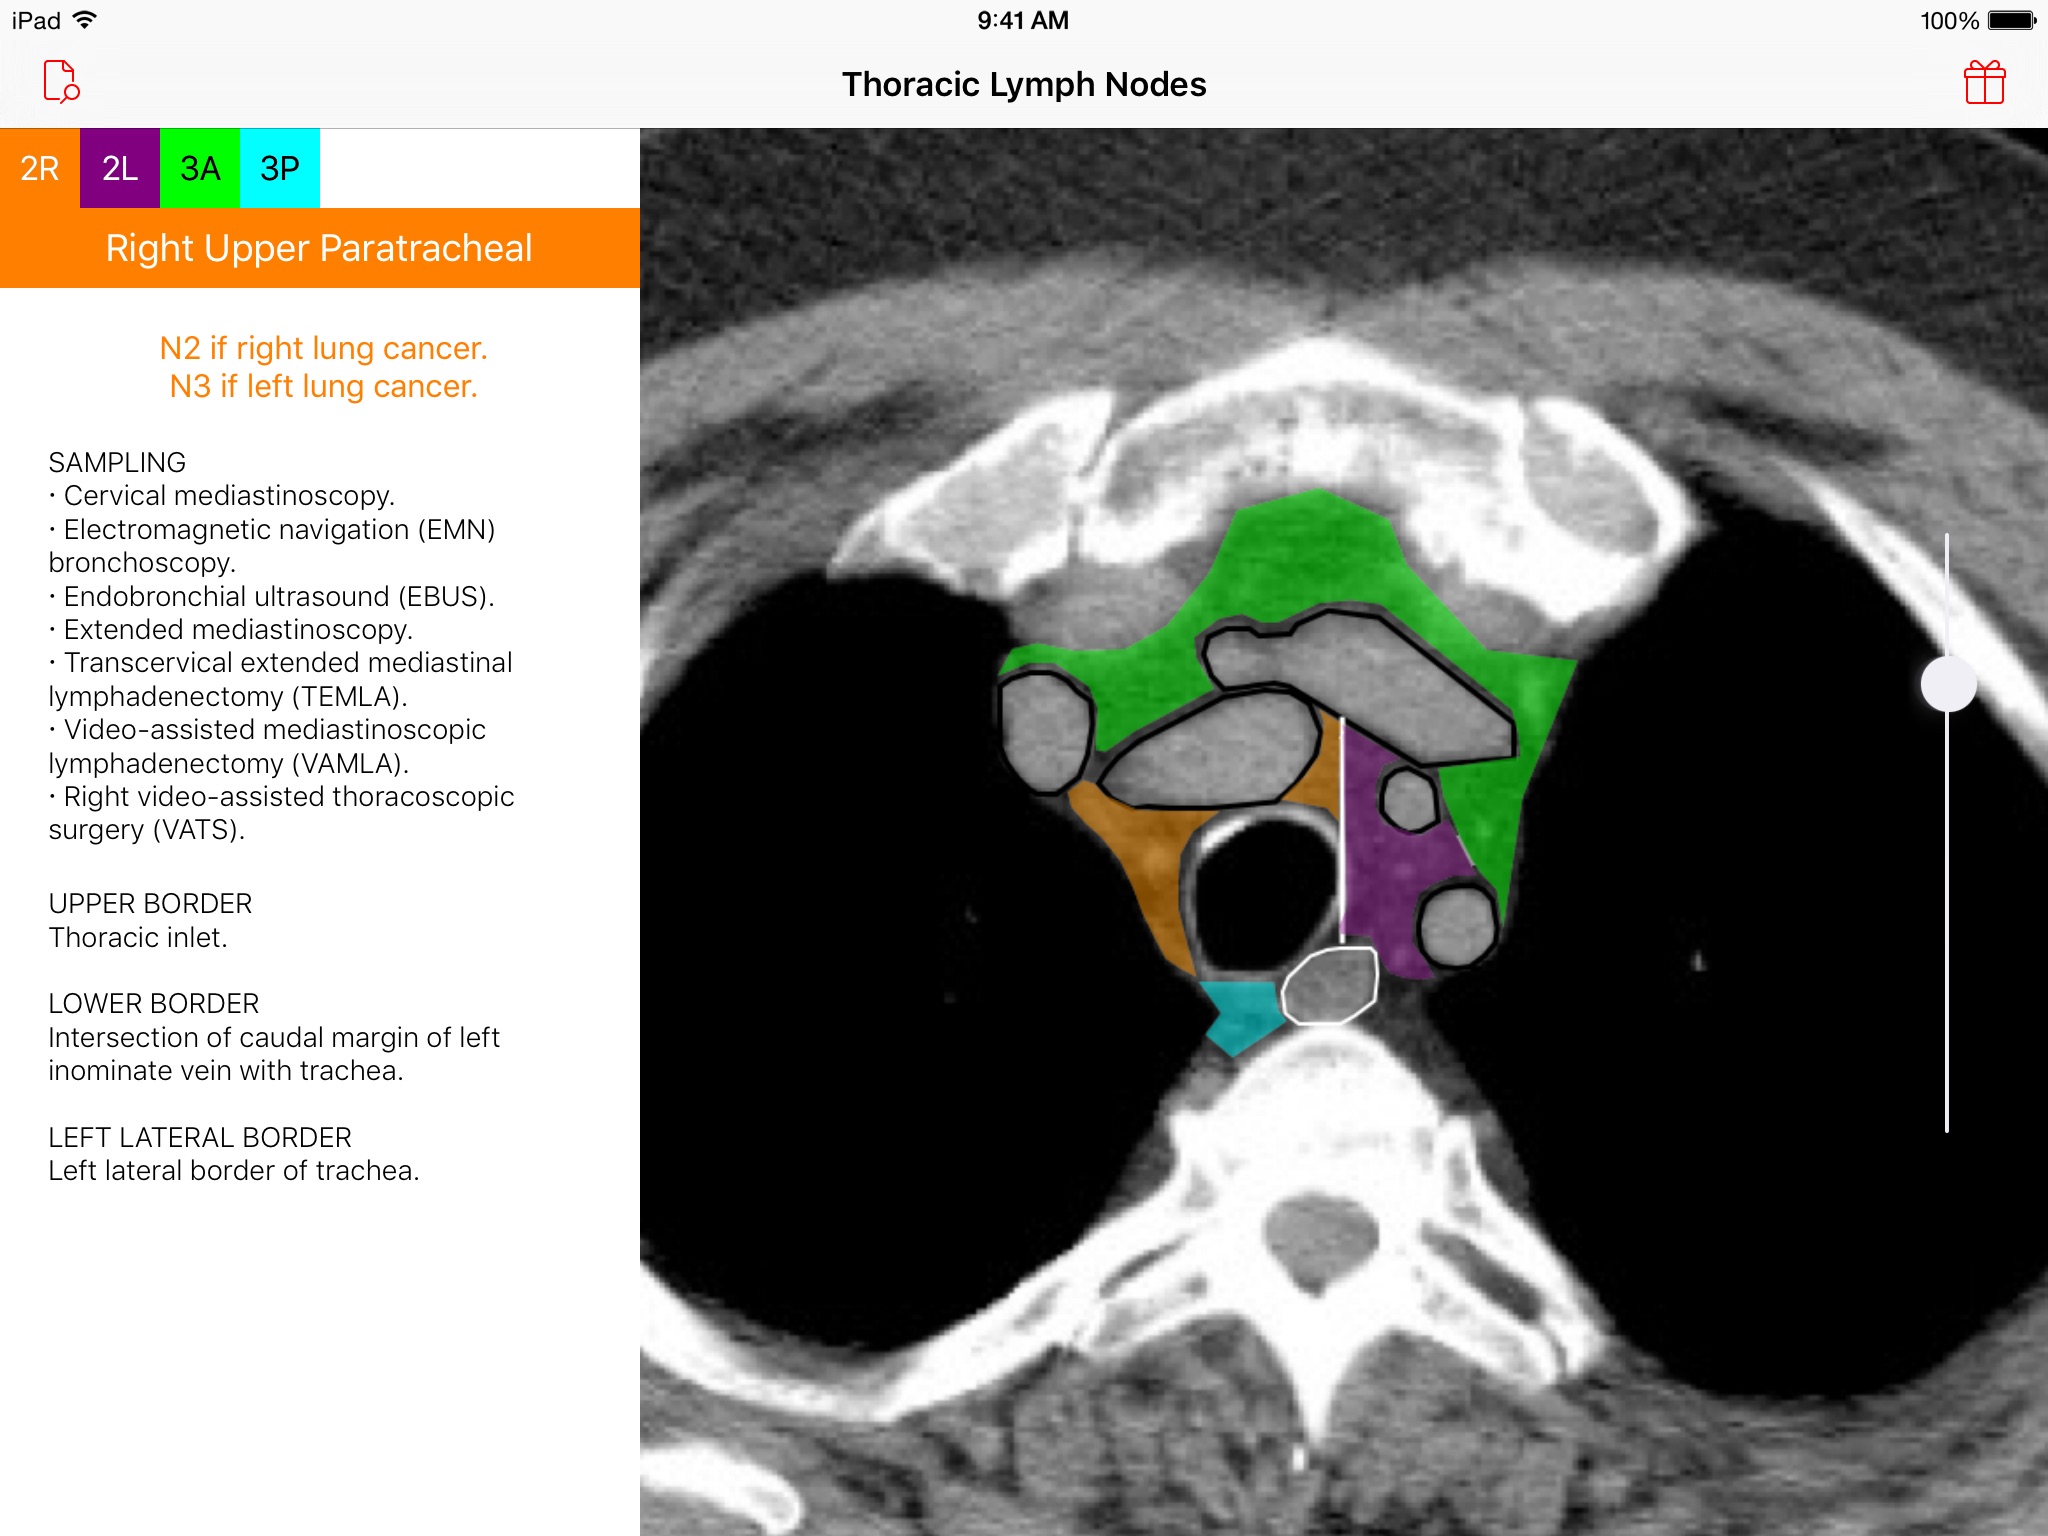

Introducing the Thoracic Lymph Node Map app, an elegant tool that provides healthcare professionals with a color-coded CT lymph node map adapted from the International Association for the Study of Lung Cancer (IASLC) lung cancer project. Effortlessly navigate through CT images of the chest and view beautifully illustrated, color-coded thoracic CT lymph node map anatomic definitions for each lymph node station. Delve deeper and learn more about classification, sampling options, and anatomic details of each lymph node station. Browse · Regional thoracic lymph node station territories · Relationships between different regional lymph node stations within the chest Discover · Clinical regional lymph node classification for each lymph node station · Sampling options for each lymph node station · Anatomic boundaries for each lymph node station Requirements · A device with iOS 8 or later This app was developed as a service to the medical community and is provided free of charge and free of advertising.